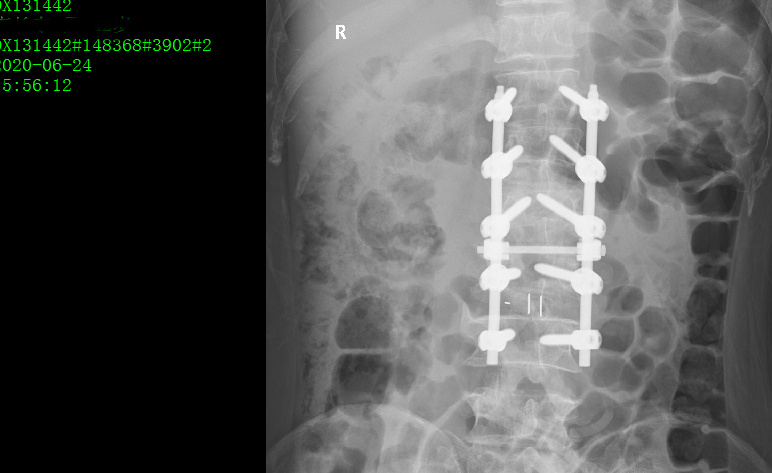

术后影像:

针对此病例诊断及治疗方案,周乙雄教授指导如下:

手术首先要考虑患者安全问题,此患者年龄偏大,心率慢(最慢38次/分),应安装起搏器,提高手术的安全度。

术中麻醉方式的选择也很重要,要选择对患者全身影响最小的麻醉方式,除腰麻外可考虑神经阻滞麻醉,必要的时候补充局部麻醉。

最后周教授表示本例病例手术做的很好,手术前对病例进行了各科室会诊,评估患者的心功能,这一点做的非常正确。

诊疗中应精准掌握手术适应症。此病例患者因外伤引起腰1、2椎体压缩骨折入院治疗,病例记载中患者有下腰部的退行性改变但没有明显椎管狭窄症状,因此手术适应症局限在腰1、2。

患者42岁尚年轻,没有明显椎管狭窄症状,将整个腰椎内固定是否范围过大。若患者高龄,下腰部有退行性改变并伴有椎管狭窄症状,可采用如此的手术操作方式,将腰3、4、5进行减压内固定。

因此医生应严格掌握手术适应症,要明确哪些手术可做,哪些手术不可做,哪些手术可做可不做,精准掌控手术适应症。